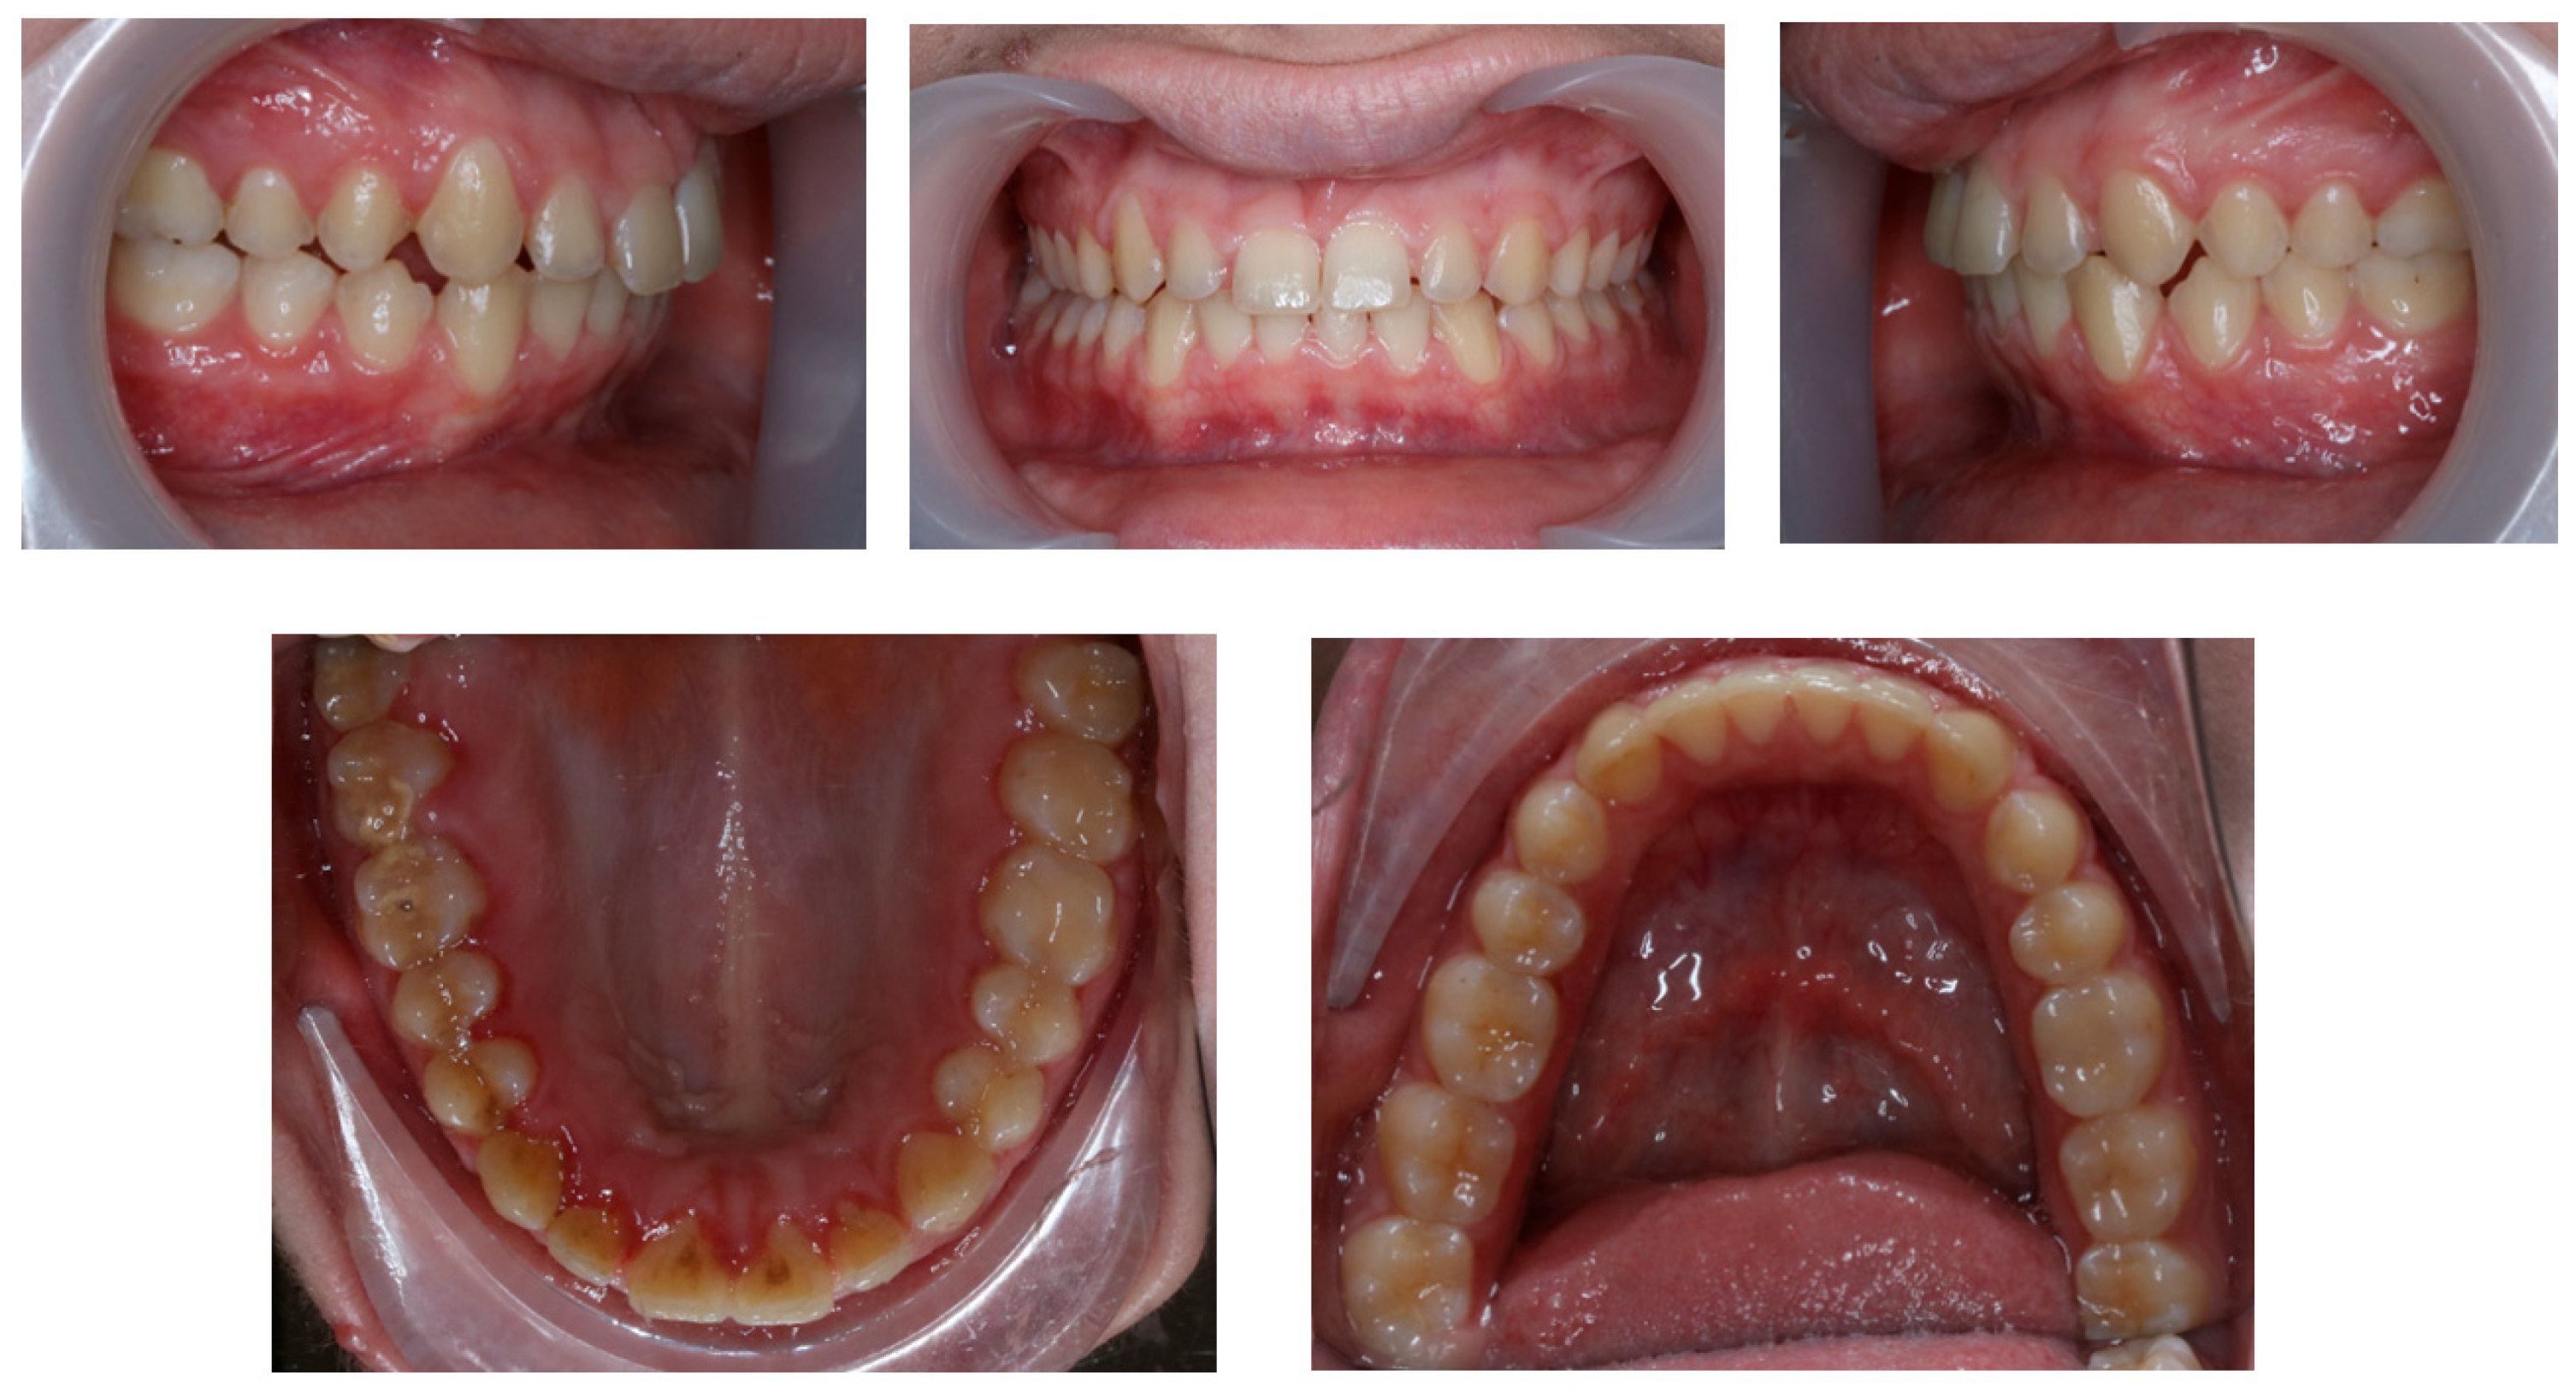

3. Results

4. Discussion